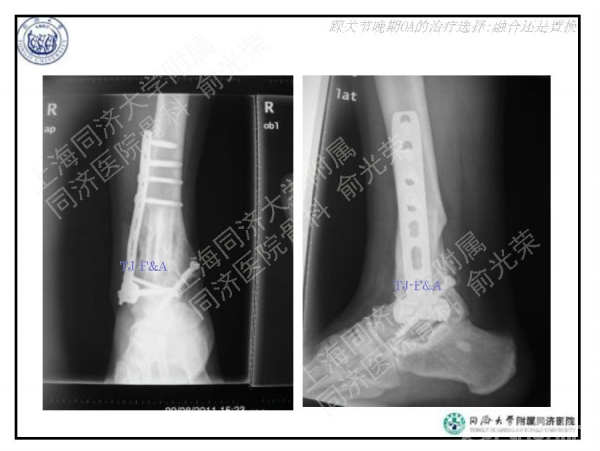

2016-01-14 文章来源:上海同济大学附属同济医院骨科 俞光荣 我要说